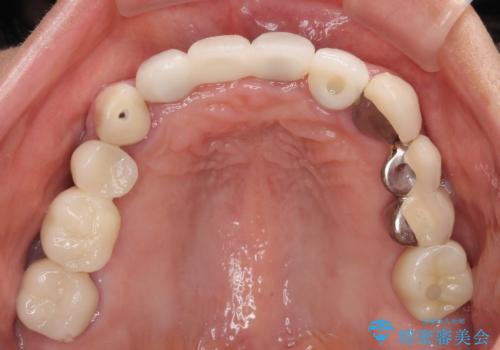

インプラントの安定度も高く、抜歯と埋入から2か月後にはオールセラミッククラウンを装着することができました。